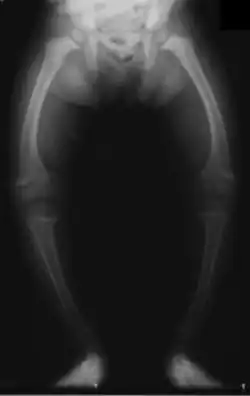

Radiograph of a child with rickets, usually caused by insufficient vitamin D

Fetuses and children who do not get enough vitamin D can result in "growth retardation and skeletal deformities."[23]